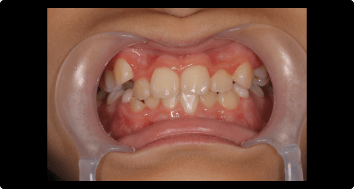

症例2:叢生の矯正治療

BEFORE

AFTER

症例概要

年代・性別

10歳代 女性

主訴

デコボコした歯並びを治したい

治療内容

ブラケット(ワイヤー)を用いた矯正治療

治療期間

4ヶ月

治療のリスク

定期検診、セルフケアを怠ると虫歯になる可能性があります

治療費用

440,000円(税込)